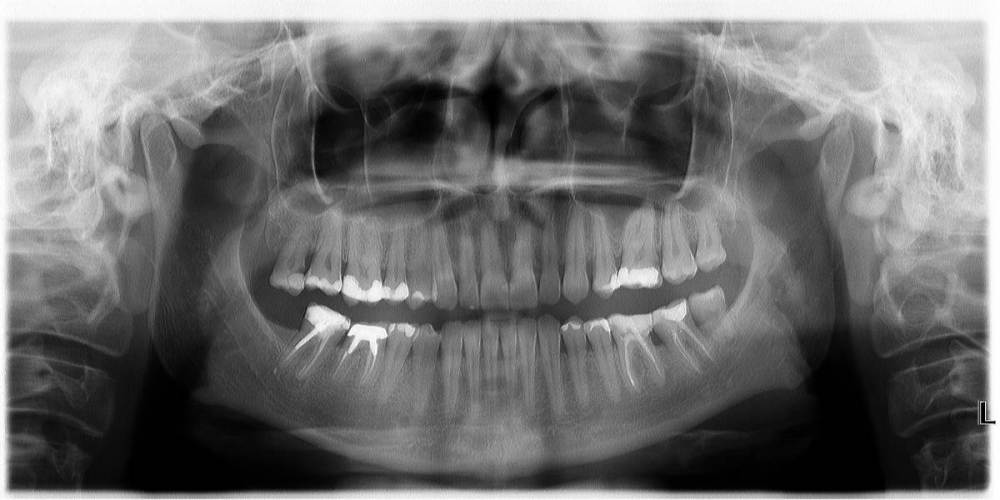

Здравствуйте. Мне 43 года. 3 Года назад перед установкой импланта пролечены были каналы 47 зуба и искуственно вывели из прикуса , чтобы небыло нагрузки , так как своей поверхности на зубе было мало. План лечения был следующий : после одномоментной имплантации  и удалению 46 зуба , сразу ставят имплант. Через 3 мес установка коронки на имплант и далее протезирование 47 зуба и введение в прикус.

Но врач ортопед  делает низкую коронку , видимо ориентируясь на 47 зуб, не беря в учет , что он не в прикусе. Переделывать отказывается , так я хожу 3 года с низкой коронкой на 46 зубе, так как мне сказали, что это норма и я должна привыкнуть , так как это искуственный зуб , и нормально , что я его не чувствую и он в прикусе. Осенью прошлого года , я все таки решила пойти к другому ортопеду , так как я так и немогла привыкнуть к этой коронке. Выяснилось , что за 3 года использования , я стерла фронт и 5 зуб и клык.  Я решила поменять коронку , но мне опять ее делают низкой . Я прошу изначально , перед слепками и объясняю ортопеду , что мне нужно выше. Но мне говорят , что врачи знают больше пациента и есть протоколы по которым действуют ортопеды , а не руководствуются ощущениями пациента.  Мне ставят коронку вновь . И вновь смыкая левую челюсть , правая у меня в воздухе. Оплачиваю , иду домой. Опять немогу жевать , жутко не удобно и мой пятый зуб задействован больше , чем 46 и 47 .

Высылаю фото отпечатков при прикусе , мою искривленную улыбку  панараму 2016 года до имплантации и сейчас. Так же ситуацию с 36.37

3 ноября  2016 год панорамный снимок полости рта .jpg